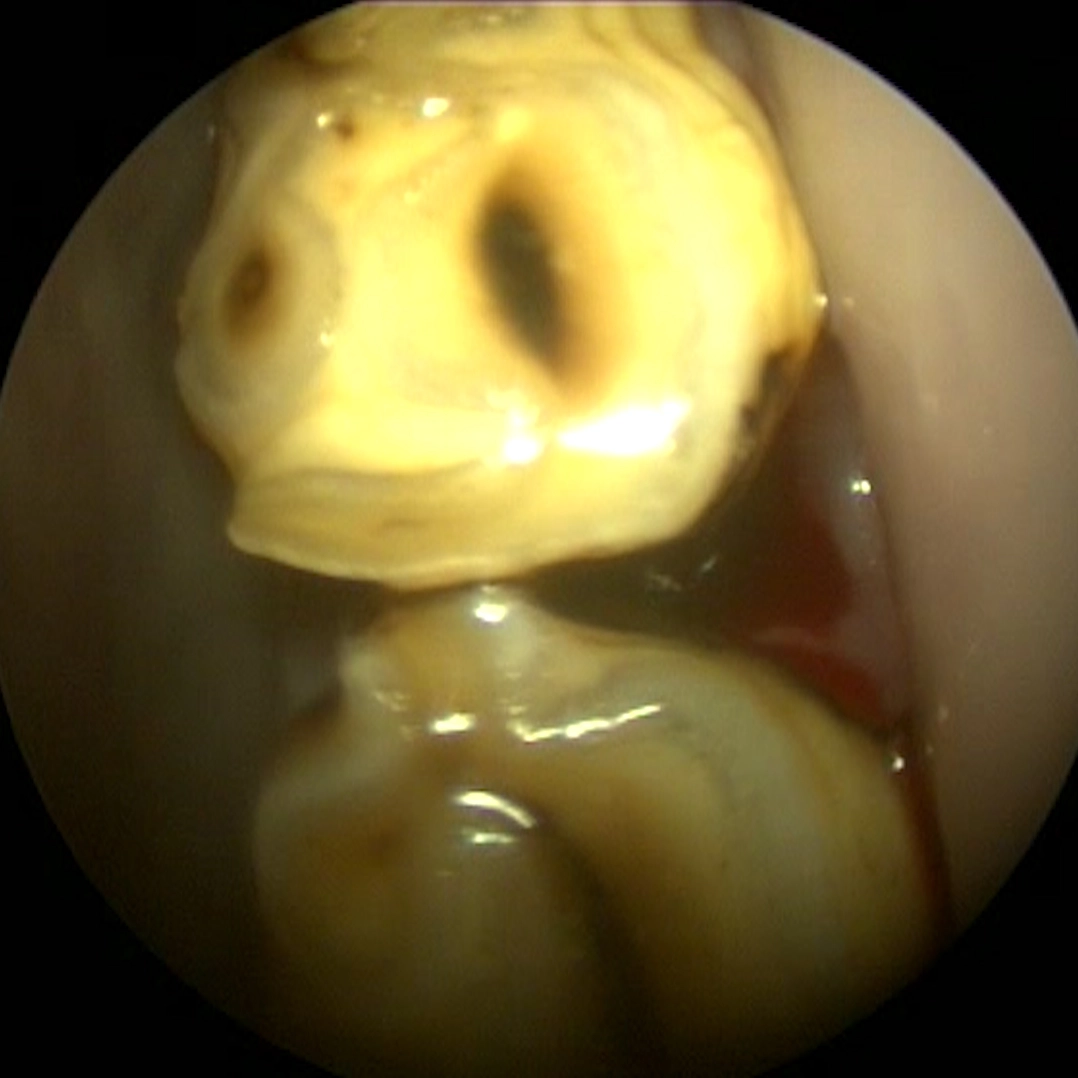

Diastema with feed impaction

Abnormal spaces between teeth allow feed material to become trapped and compressed into the gum tissue.

Over time, this leads to inflammation, infection, and damage to supporting structures if not addressed.